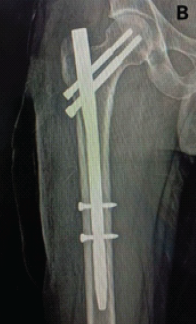

Aneurysmal Bone Cyst Presenting as a Pathological Subtrochanteric Femur Fracture in an Adolescent: A Case Report

Chandrashekhar R Rai , Sandeep V Gavhale , Vijaysing Chandele , Alok P Yadav , Chinmay S Torne , Vishal B Karpe